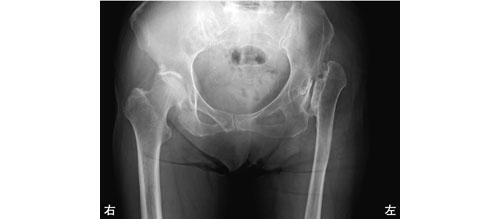

3

患者の股関節部エックス線写真を示す。大腿骨および下腿骨に骨折はなく、膝関節の変形や可動域制限はない。右大腿長44.0 cm、両側の下腿長35.5 cm、右下肢の棘果長83.0 cmであった。左下肢の肢長検査で正しいのはどれか。

1

棘果長 81.0 cm ――― 転子果長 79.5 cm

2

棘果長 81.0 cm ――― 転子果長 78.5 cm

棘果長 81.0 cm ――― 転子果長 77.5 cm

4

棘果長 83.0 cm ――― 転子果長 79.5 cm

5

棘果長 83.0 cm ――― 転子果長 77.5 cm